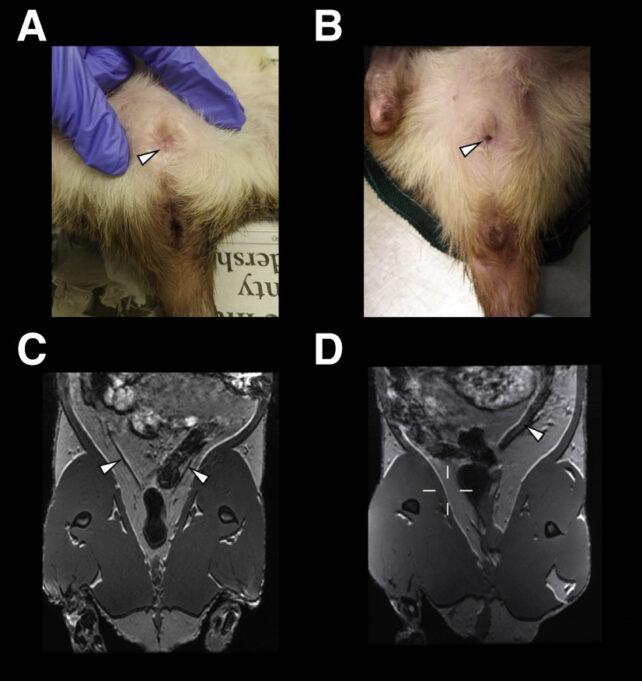

Bilim insanları, vajinasını açıp kapatabilen dev Afrikalı keseli sıçanlarıyla ilgili bir çalışma yaptı. 27 Mart'ta Current Biology adlı hakemli bilimsel dergide yayımlanan araştırmada, yetişkin hayvanlarda bir zamanlar sabit olduğu düşünülen özelliklerin bazı koşullarda nasıl değişken hale gelebileceği incelendi.

Dev Afrikalı keseli sıçanların vajina girişi, diğer çoğu memelinin aksine yetişkinliğe kadar kapalı. Bu hayvanlar doğum yaptıktan sonra bile vajinasını açıp kapatabiliyor.

Dev Afrikalı keseli sıçanlarından mayın ve bombaların tespitinde yararlanılıyor. Bu hayvanlar tüberkülozu da saptayabiliyor. Araştırmacılar önemli özellikleri sebebiyle üremesini istese de bu hayvanları yüksek oranda yetiştirmek zor. Buradan hareket eden Cornell Üniversitesi'nden uzmanlar, 51 dişi dev Afrikalı keseli sıçanını analiz etti.

17 sıçanda 23 kez üreme durumlarının değiştiği, yani vajinanın açılıp kapatıldığı görüldü. Üreme dönemindeki bir dişi öldüğünde, 7 sıçanın vajinasının açıldığı tespit edildi.

Ayrıca vajinası açık ve kapalı dişilerin vücut kütlesi ve uzunluğunun farklı olmadığı belirlendi. Ancak vajina derinliği, meme ucu boyutu ve rahim genişliği açısından değişiklik gösterdiği kaydedildi. İki grubun idrarında ve dışkısındaki bileşikler de epey farklıydı.